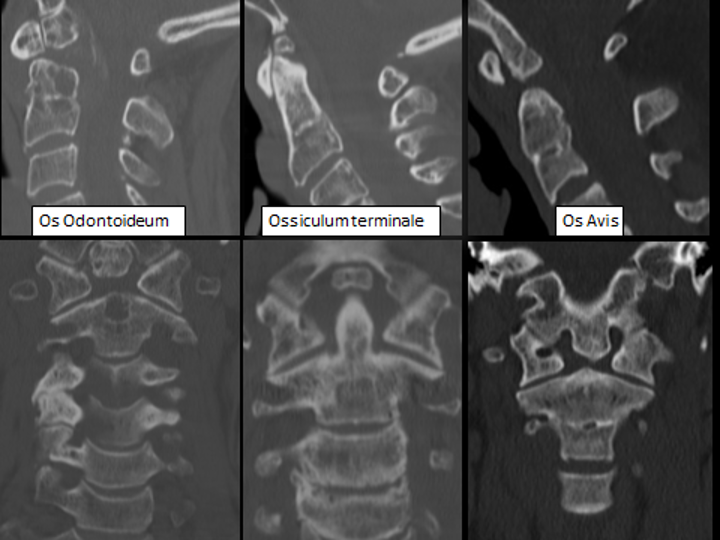

Os Odontoideum

Ossiculum terminale

OS Avis

Apical and basal segments are separated

Basal and segments are thinly connected

The apical dental segment is attached to the basioccipital and is not fused to the main dental stem.

Disturbance of intervertebral boundary mesenchyme of C1 and C2 axial sclerotome

Disturbance of intervertebral boundary mesenchyme of Pro atlas and C1 axial sclerotome

Abnormal resegmentation of proatlas axial sclerotome

Can be unstable

Mostly Stable

Can cause compression

Can cause compression≈

notion image